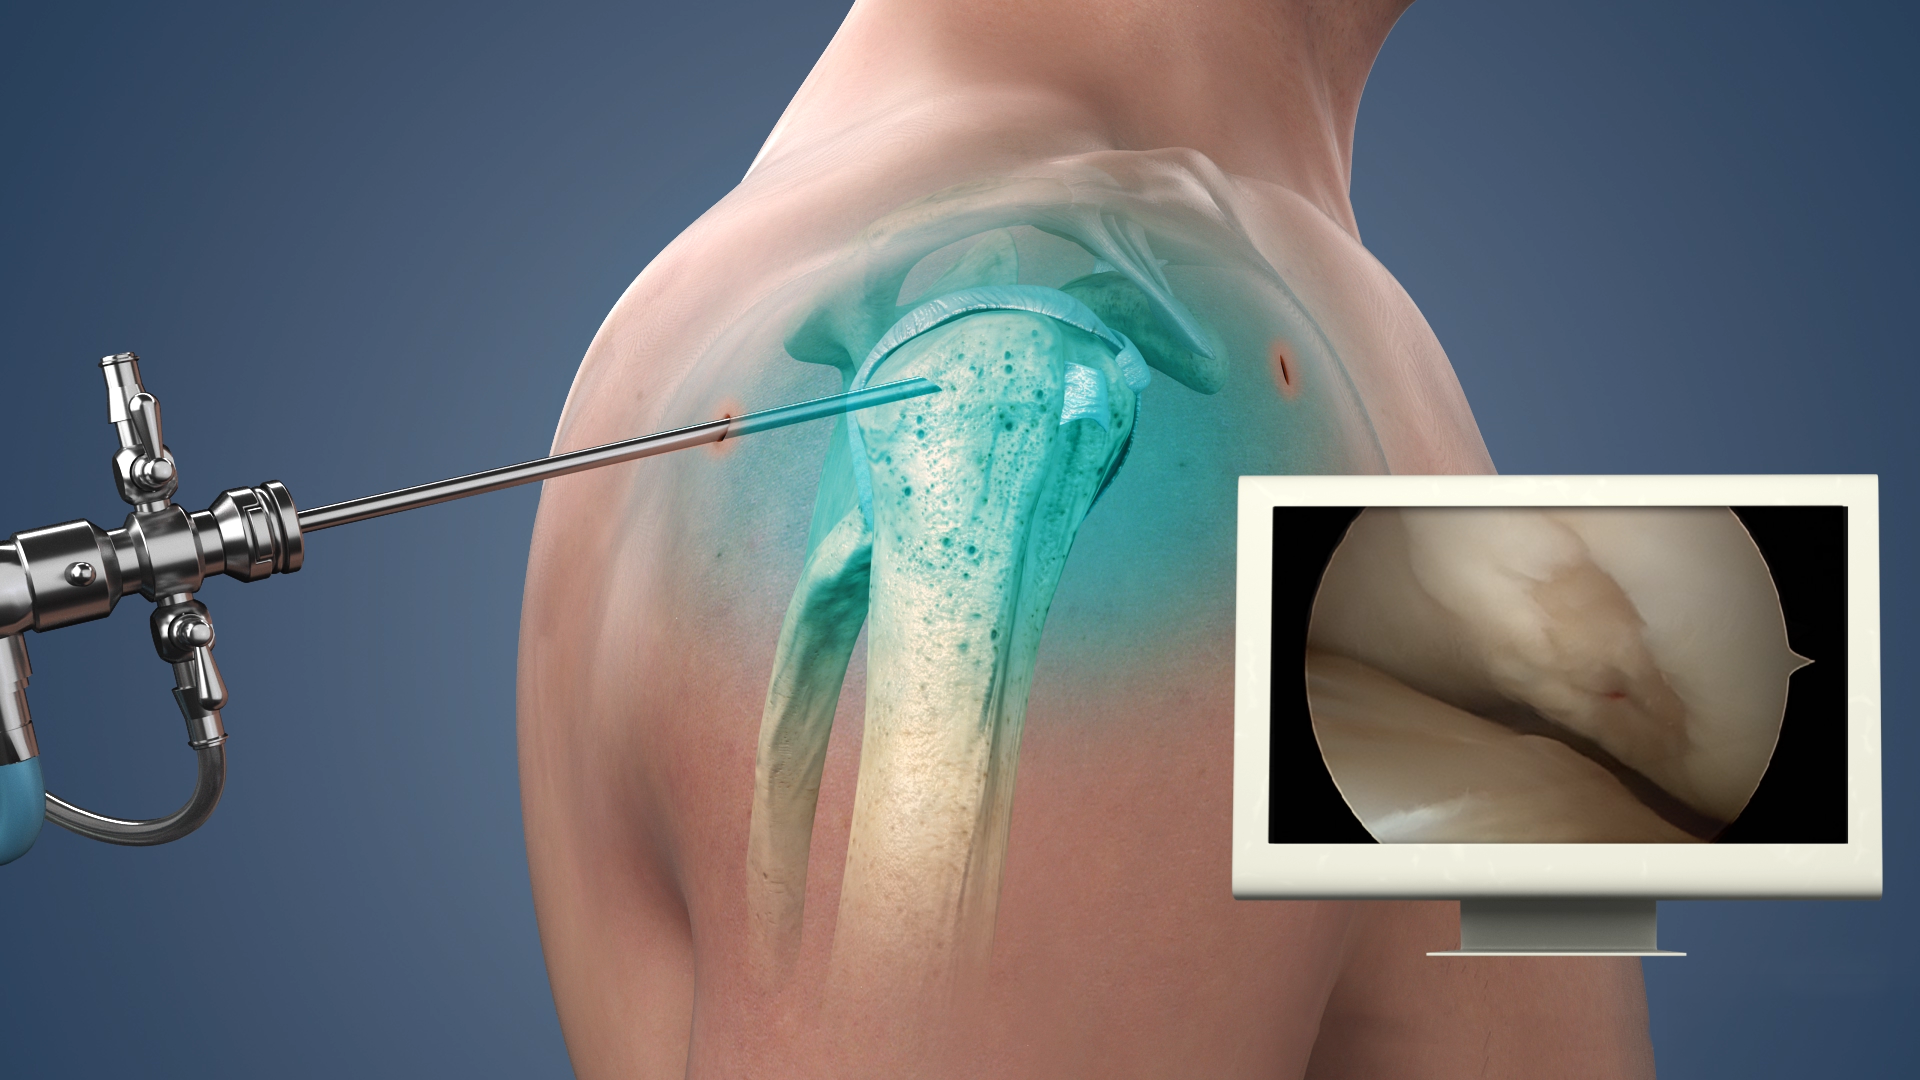

Shoulder arthroscopy is a highly demanding technique and we provide excellent skilful management of shoulder problems by arthroscopy (key hole surgeries). Conditions like frozen shoulder, rotator cuff tears (supraspinatus /infraspinatus /subscapularis), Bankart’s lesion/ shoulder instability, SLAP lesion, associated hill such lesion etc.

There is often a debate among patients and surgeons about which is better, arthroscopic or 'open' surgery. Open surgery, a procedure using larger incisions and enabling the surgeon to look inside the joint, may be better for certain procedures under certain circumstances. Arthroscopic surgery has some advantages-smaller incisions, less tissue damage-but these are usually not helpful if the overall procedure cannot be performed as well. You need to discuss with your surgeon if a particular procedure can be done arthroscopically.

Treatment of rotator cuff tears is done with shoulder arthroscopy. In some cases, open procedure may be performed as an intraoperative/ preoperative decision to obtain best results